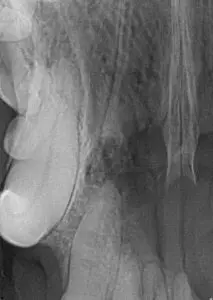

The image above shows one year old Deutsch Draahthaar with a supernumerary (extra) right mandibular 1st premolar that was unerupted and under the gumline. Impossible to know it existed without intra-oral imaging.